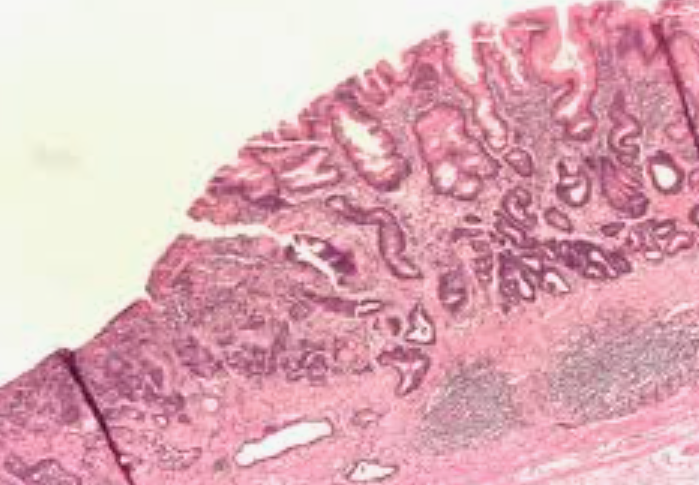

장상피화생이란 무엇일까?

장상피화생은 위 점막 세포가 장 점막처럼 변하는 현상을 말해요. 만성 염증으로 위가 손상되다 보니, 재생 과정에서 원래 세포 대신 소장이나 대장 세포가 자리 잡는 거죠.